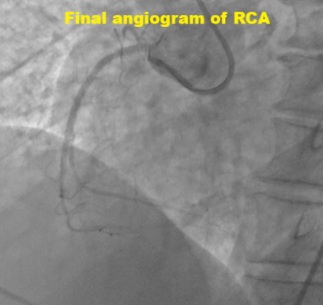

Dual access via right radial and femoral arteries. Failed to cross antegradely the proximal cap CTO using UltimateBros3 and Fielder XT-R guidewires / Corsair Pro, and retrogradely via septals collateral. Initially decided to abandon the procedure as deem small RCA vessel size. Unfortunately noted coronary perforation at proximal RCA CTO site, temporary tamponade with microcatheter. Retrograde Suoh3 wire via LAD epicardial collateral successfully crossed the distal cap of proximal RCA CTO, however, Caravel microcatheter unable to pass through the distal RCA branch for better support. Gladius EX14 guidewire supported with Corsair Pro microcatheter swiftly crossed the proximal cap antegradely (using the Suoh3 as the guide from retrograde) successfully till distal RCA branch. Caravel and Suoh3 removed retrogradely without complication. Predilate the RCA (prolonged balloon inflation) using SC 2.0x15mm (6-8atm, 3mins each) - to facilitate the plaque sealing of the perforation site. IVUS performed confirmed the wire in the true lumen. Stented with 2 overlapping DES 2.25x33mm (nominal) and 3.0x33mm (nominal). Noted the stent was from RCA-acute marginal branch, distal RCA was smaller vessel. Post-dilated distal stent with NC 2.5x15mm (nominal) while proximal stent with NC 3.0mm and NC 4.0mm. IVUS performed good stent apposition/expansion, with satisfactory MSA. Good angiographic result, TIMI 3 flow, no dissection/perforation noted. No pericardial effusion from echocardiography.

His hemodynamic was stable throughout the procedure. He was discharged from ward the next day. Clinical follow in clinic, he remained asymptomatic. Retrograde approach via the epicardial collateral remained a high risk route for PCI. Precaution to prevent untoward complication. This case demonstrated the salvage of the coronary perforation at RCA CTO via the LAD epicardial collateral.